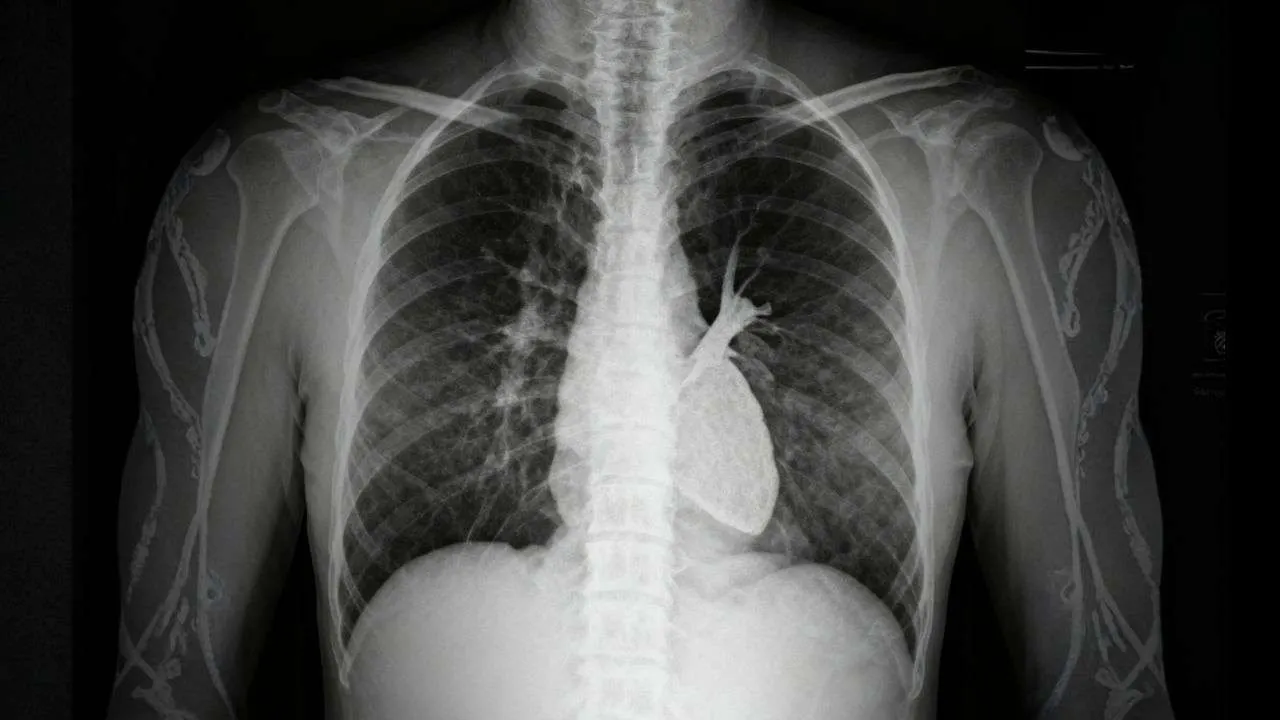

Have you ever wondered how doctors spot life-threatening conditions like pneumothorax or pneumonia on a seemingly simple black-and-white chest image? The ability to accurately perform chest x-ray interpretation is one of the most critical skills that separates confident clinicians from anxious medical students. Whether you’re an MBBS student preparing for clinical exams, a junior doctor building diagnostic confidence, or simply someone curious about how medical imaging works, mastering the systematic approach to reading chest radiographs will transform how you understand respiratory and cardiac pathology.

Chest radiography remains the most commonly ordered imaging study worldwide, with over 70 million chest X-rays performed annually in the United States alone. Despite advances in CT and MRI technology, the humble chest X-ray continues to be the first-line investigation for countless respiratory, cardiac, and thoracic conditions. Studies show that medical students and junior doctors often struggle with chest x-ray interpretation, with accuracy rates as low as 40% when clinical history is absent. This comprehensive guide will equip you with the systematic tools, clinical pearls, and confidence-building strategies you need to excel at chest x-ray interpretation in both academic and real-world settings.

Chest x-ray interpretation is the systematic process of analyzing a chest radiograph to identify normal anatomical structures and detect pathological abnormalities affecting the thorax. According to standard radiology textbooks like “Felson’s Principles of Chest Roentgenology,” chest radiograph interpretation involves evaluating the lungs, heart, mediastinum, pleura, bones, and soft tissues using a structured approach that minimizes the risk of missing critical findings.

The process requires understanding basic radiographic principles: Chest X-rays are a form of electromagnetic radiation that pass through the body differently depending on tissue density. Dense structures like bones and the heart appear white (radiopaque), while air-filled lungs appear black (radiolucent). This density difference allows visualization of anatomical structures and pathological processes. The systematic approach to chest x-ray ensures that every component is evaluated methodically, preventing satisfaction of search bias where finding one abnormality causes you to stop looking for others.

Understanding normal chest x-ray anatomy is essential before identifying pathology. Let’s break down the key anatomical landmarks: